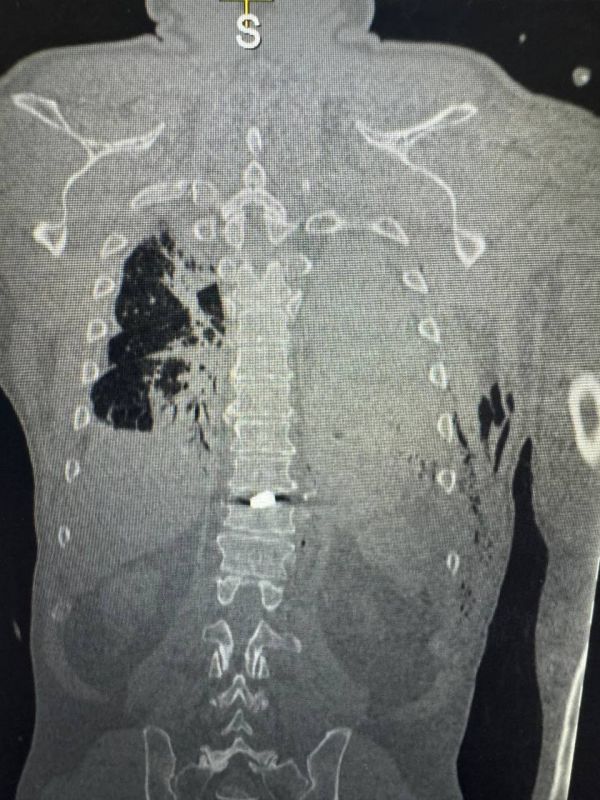

Пациент Генической больницы с осколочным ранением позвоночника направлен на специализированное лечение в ДонецкКак сообщили "Таврии" в региональном минздраве, в Геническую ЦРБ был госпитализирован мужчина в тяжелом состоянии, получивший минно-взрывную...

Житель Новой Каховки с осколочным ранением позвоночника направлен на лечение в Донецк, сообщили "Таврии" в минздраве регионаВ Геническую ЦРБ был госпитализирован мужчина с минно-взрывной травмой, полученной из-за обстрела ВСУ. По...

Пациент Генической больницы с осколочным ранением позвоночника направлен на специализированное лечение в ДонецкВ Геническую центральную районную больницу был госпитализирован житель Новой Каховки — мужчина получил минно-взрывную травму...